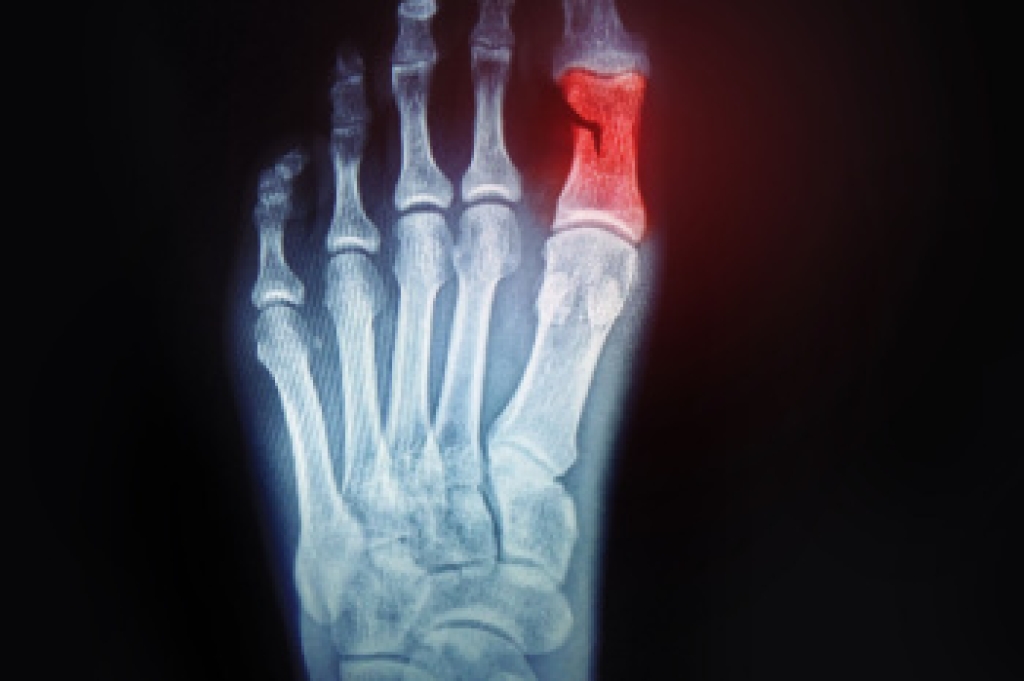

Risks and Causes of MTP Joint Pain

The toes are connected to the long bones of the foot with metatarsophalangeal, or MTP, joints. These joints are essential for balance and forward motion while walking. Pain in this area, most often in the big toe, develops when the joint is exposed to excess stress, poor alignment, or conditions that cause inflammation. Common causes include bunions, turf toe, and certain forms of arthritis like gout, osteoarthritis, and rheumatoid arthritis. MTP joint problems can lead to swelling, stiffness, and tenderness that make it difficult to walk or stand comfortably. Risk factors include chronic inflammatory disease and foot or leg misalignment. Wearing shoes that lack adequate support or place pressure on the toes, such as high heels or narrow footwear, are other factors. A podiatrist can assess the underlying cause and provide effective treatment to reduce pain and improve alignment. If you have ongoing pain in an MTP joint, it is suggested that you make an appointment with a podiatrist for an exam and treatment options.

What Causes Toe Pain?

Most severe toe pain is caused due to a sports injury, trauma from dropping something heavy on the toe, or bumping into something rigid. Other problems can develop over time for various reasons.

Toe pain can be caused by one or more ailments. The most common include:

- Trauma

- Sports injury

- Wearing shoes that are too tight

- Arthritis

- Gout

- Corns and calluses

- Hammertoe

- Bunions

- Blisters

- Ingrown toenails

- Sprains

- Fractures (broken bones)

- Dislocations

When to See a Podiatrist

- Severe pain

- Persistent pain that lasts more than a week

- Signs of infection

- Continued swelling

- Pain that prevents walking

Diagnosis

In many cases the cause of toe pain is obvious, but in others, a podiatrist may want to use more advanced methods to determine the problem. These can range from simple visual inspections and sensation tests to X-rays and MRI scans. Prior medical history, family medical history, and any recent physical traumatic events will all be taken into consideration for a proper diagnosis.

Treatment

Treatments for toe pain and injuries vary and may include shoe inserts, padding, taping, medicines, injections, and in some cases, surgery. If you believe that you have broken a toe, please see a podiatrist as soon as possible.